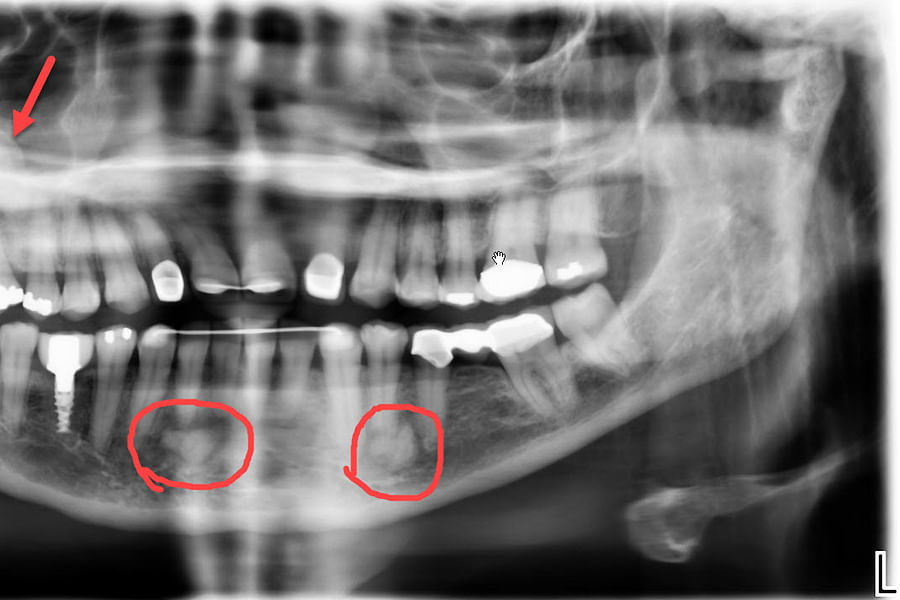

Dental X-rays are more than just tools for diagnosing cavities; they provide a comprehensive view of your oral health status. By allowing dentists to detect problems before they become severe, these images can save patients time, money, and discomfort in the long run. Early detection through modern imaging technology can reveal hidden decay between teeth, bone loss due to gum disease, or even cysts and tumors that are not visible during a standard exam.

- Tumors - Spotting abnormal growths or cysts within the jawbone.

- Bone Loss - Evaluating the extent of bone loss associated with osteoporosis or other conditions.

Despite the myths surrounding dental x-rays, they play an integral role in preventative dentistry. X-rays allow dentists to detect issues that are not visible during a standard oral exam. This includes early signs of decay between teeth, problems below the gum line, and changes in bone density that could indicate periodontal disease. By identifying these problems early, fundamental dental treatments can be administered promptly, saving patients from more extensive and costly procedures down the line.